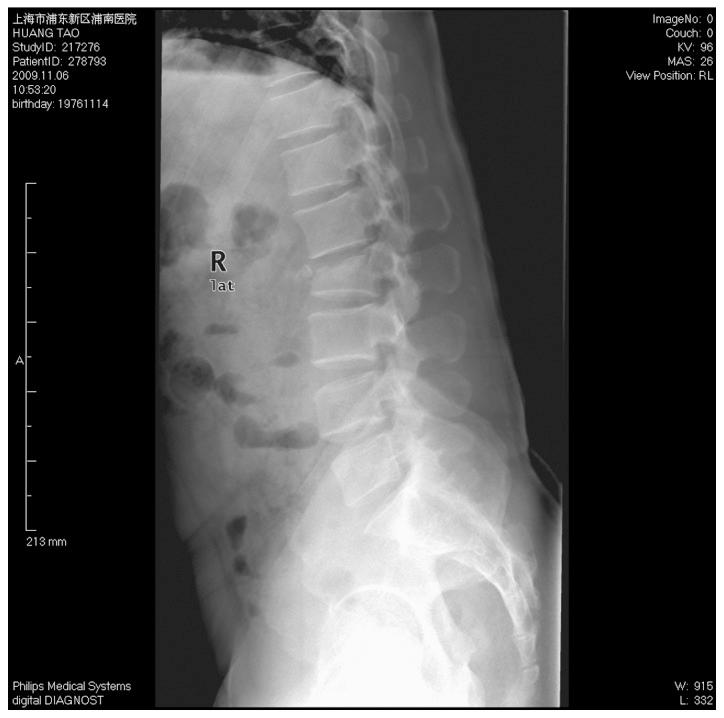

椎弓根螺钉内固定治疗胸腰椎骨折中骨折椎体的疗效分析

Efficacy analysis of pedicle screw internal fixation of fractured vertebrae in the treatment of thoracolumbar fractures.

The present study aimed to discuss the method and effect of posterior internal fixation of thoracolumbar fractures strengthened by the vertical stress pedicle screw fixation of fractured vertebrae. Patients with single thoracolumbar fractures were examined retrospectively. Fourteen patients (group A) had been treated with vertical stress pedicle screw fixation of a fractured vertebra and sixteen patients (group B) received traditional double-plate fixation, as a control. All patients were diagnosed with fresh fractures with a complete unilateral or bilateral pedicle and no explosion of the inferior half of the vertebral body or inferior endplate. In group A, patients received conventional posterior distraction and lumbar lordosis restoration, as well as pedicle screws in the fractured vertebra in a vertical direction to relieve stress to achieve a local stress balance. All patients were followed up postoperatively for 4-18 months (average, 12.6 months). The vertical stress pedicle screw fixation assisted in the reduction of vertebrae fracture, which reduced the postoperative Cobb's angle loss. There was a significant difference in the change of Cobb's angle between the two groups one year after surgery (P<0.01). Conditional application of pedicle screws in a single thoracolumbar fracture enhances the stability of the internal fixation system and is conducive to the correction of kyphosis and maintenance of the corrective effects.

摘要

本研究旨在探讨通过骨折椎体垂直应力椎弓根螺钉固定加强胸腰椎骨折后路内固定的方法及效果。对单节段胸腰椎骨折患者进行回顾性研究。14例患者(A组)采用骨折椎体垂直应力椎弓根螺钉固定治疗,16例患者(B组)接受传统双钢板固定作为对照。所有患者均诊断为新鲜骨折,单侧或双侧椎弓根完整,椎体下半部及终板无爆裂。A组患者接受传统后路撑开及腰椎前凸恢复,并在骨折椎体垂直方向置入椎弓根螺钉以缓解应力,实现局部应力平衡。所有患者术后随访4 - 18个月(平均12.6个月)。垂直应力椎弓根螺钉固定有助于椎体骨折复位,减少术后Cobb角丢失。术后1年两组Cobb角变化差异有统计学意义(P<0.01)。单节段胸腰椎骨折有条件地应用椎弓根螺钉可增强内固定系统稳定性,有利于后凸畸形的矫正及矫正效果的维持。